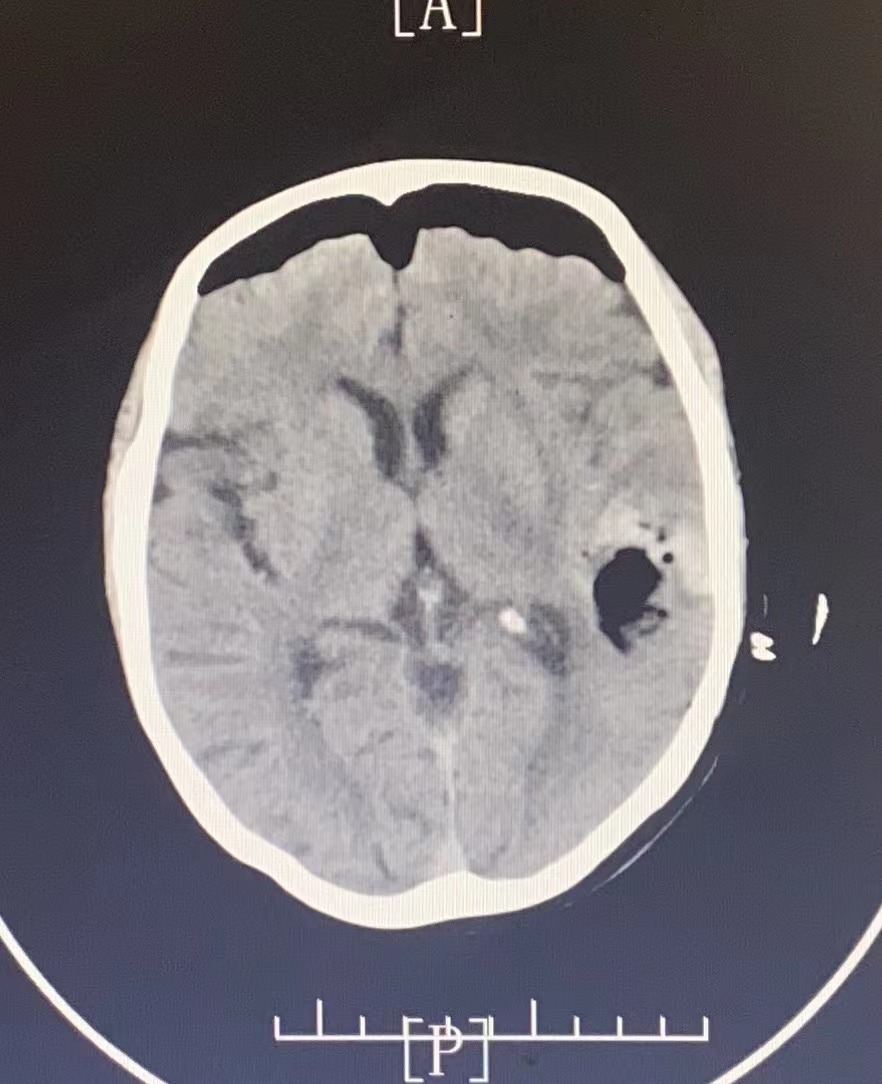

輔助檢查:頭部CT提示左側基底節(jié)區(qū)腦出血。

圖片

手術前

患者行神經(jīng)內(nèi)鏡下腦出血清除術,術后瞳孔等大等圓,對光反應存在。術后第1天患者即可刺痛睜眼、握手。

手術后